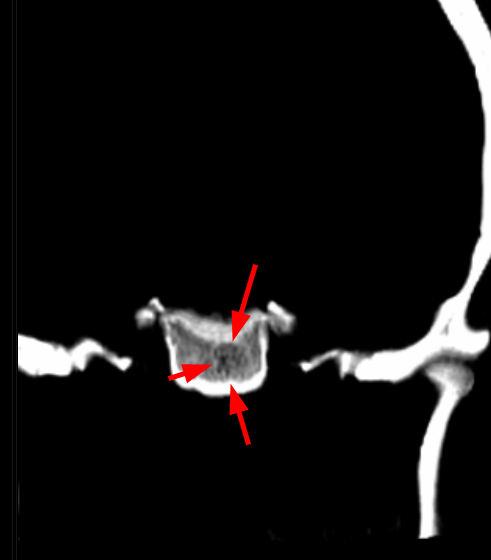

*Clue: Typical trabecular (“polka-dot”) pattern on CT

💡 Why Polka-Dot Pattern on CT?

Bone trabeculae preserved between vascular channels

Small round densities on axial CT

Key differential diagnostic feature